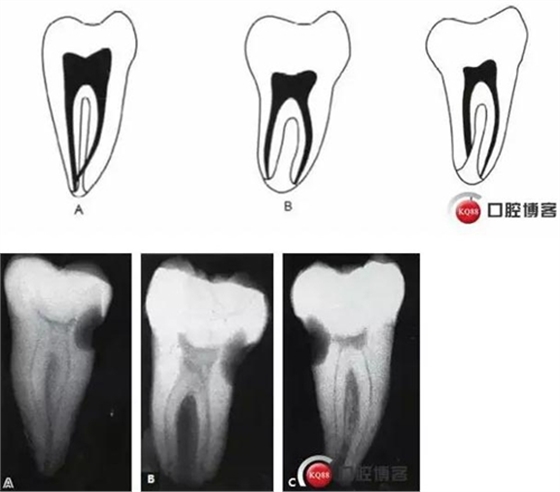

傳統(tǒng)的Melton C形根管分類法雖深化了對(duì)根管結(jié)構(gòu)的認(rèn)識(shí),但由于是基于組織學(xué)的分類,不能指導(dǎo)臨床實(shí)踐。有學(xué)者基于C形根管X 線特征,結(jié)合顯微CT掃描結(jié)果,提出了一種新的分類方法,便于臨床應(yīng)用。

這種分類方法將下頜第二磨牙分為3 型:

I型:融合型,X線片上見2個(gè)根管,但在根尖區(qū)融合。

II型:分離型,X線片見2個(gè)根管且互相獨(dú)立。

III型:不對(duì)稱型,X線片上雖有2個(gè)根管互相獨(dú)立,但一長一短,互不對(duì)稱。